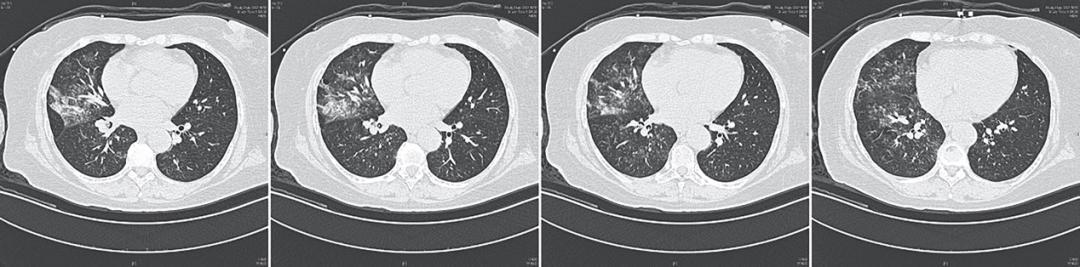

56岁中年女性,因「梦里与丈夫吵架」,醒来后咯血10余次,每次量约50ml,伴有明显胸闷、憋气,求诊于清华长庚医院呼吸与危重症医学科牟向东主任的门诊,牟主任给患者完善了胸部CT(图1),发现右肺中下叶多发团片影及磨玻璃影,右肺主支气管内可见占位堵塞气道。考虑右肺病变为肺泡内出血可能性大,不除外肿瘤或感染性病变。

图1:患者入院胸部CT影像